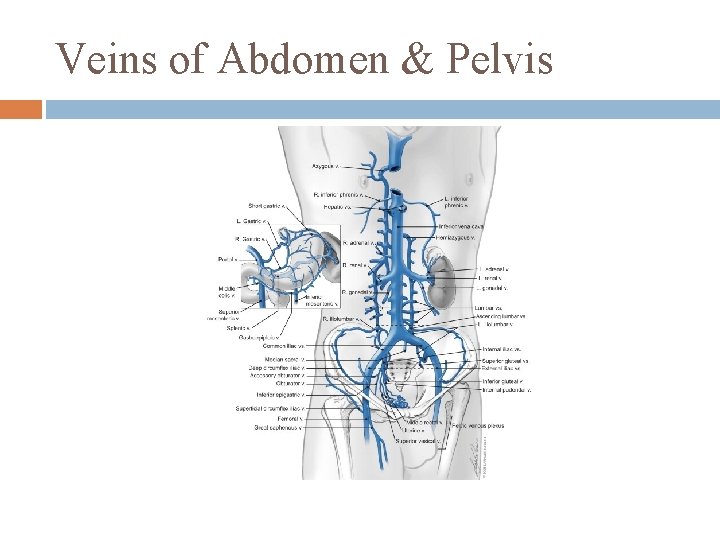

Veins of Abdomen & Pelvis